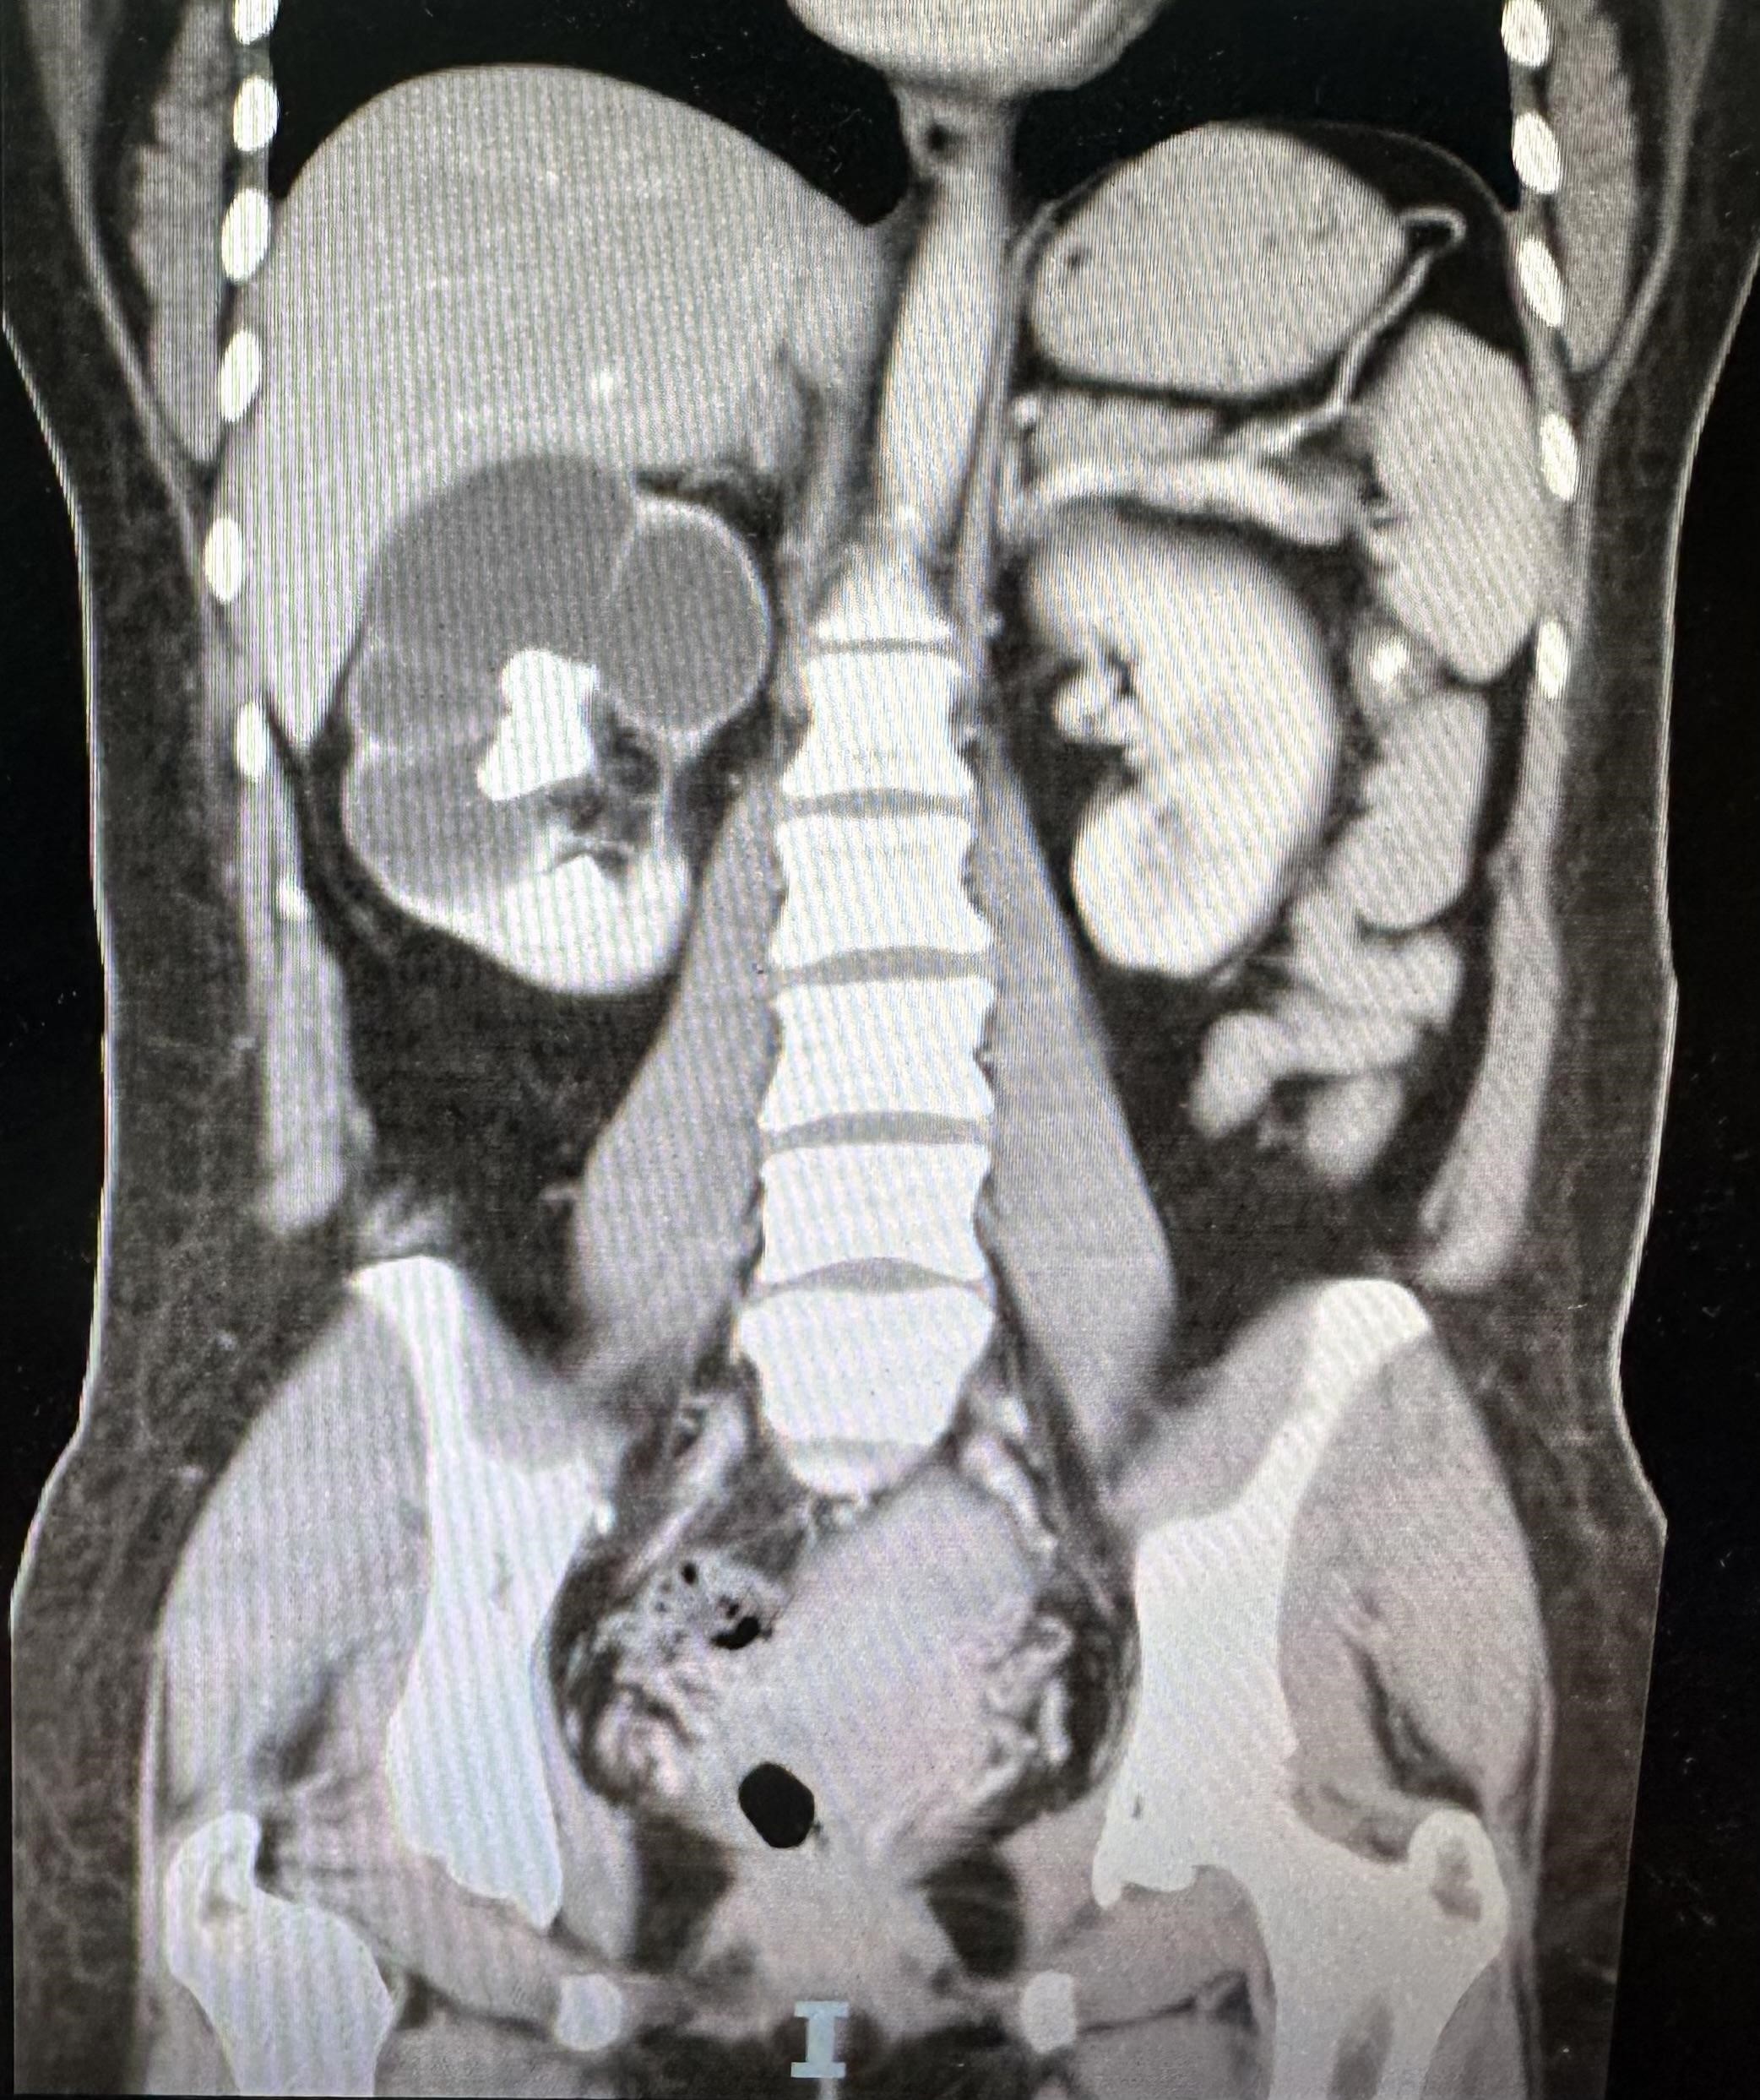

El hallazgo llamativo del estudio lo condiciona la presencia de hidronefrosis severa del riñón derecho (Figura 2) que se asocia a importante disminución del grosor cortical y signos de dilatación pielocalicial, que es condicionado por la presencia de una imagen hiperatenuante que ocupa completamente la pelvis y los cálices renales, adoptando una morfología ramificada (Figura 3a) y muestra densidad heterogénea mayormente hiperdensa que oscila entre los 950 y 1280 UH. El hallazgo sugiere obstrucción urinaria prolongada con probable compromiso funcional del parénquima renal (Figura 3b).

Imagen 2: Tomografía axial del abdomen y pelvis. Se observa adelgazamiento cortical y pérdida de la diferenciación corticomedular del riñón derecho por severa hidronefrosis, hallazgos sugerentes de daño estructural renal crónico. Compárese con la morfología conservada del riñón contralateral. Fuente: departamento de radiología médica del Hospital Regional Dr. Rafael Hernández.

Figura 3a y 3b.Tomografía coronal del abdomen y pelvis. a) Cálculo hiperdenso de gran tamaño, con morfología ramificada, que ocupa por completo la pelvis renal y se extiende a los cálices mayores y menores del riñón derecho. La litiasis replica con precisión la arquitectura del sistema pielocalicial, característica de una litiasis coraliforme completa. b) En contraste, el riñón izquierdo presenta tamaño, morfología y grosor cortical conservados, sin evidencias de dilatación ni litiasis, actuando como unidad funcional compensadora. Fuente: departamento de radiología médica del Hospital Regional Dr. Rafael Hernández.